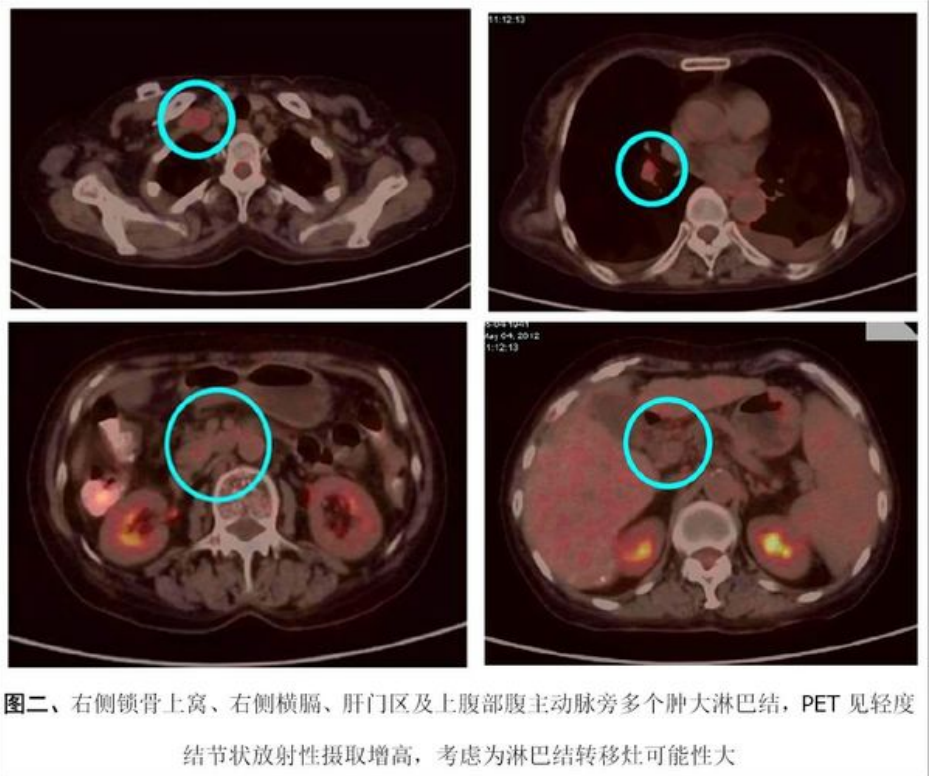

2012-5-4行PET/CT检查,结果如下:

9.png

10.png

11.png